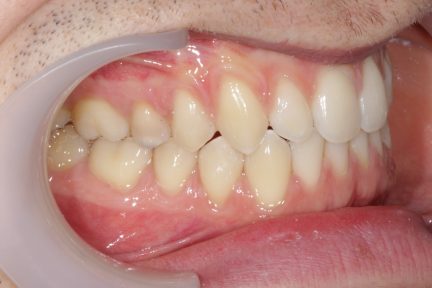

Classe III, articulé croisé antérieur, béance, espacement, diastème

État initial